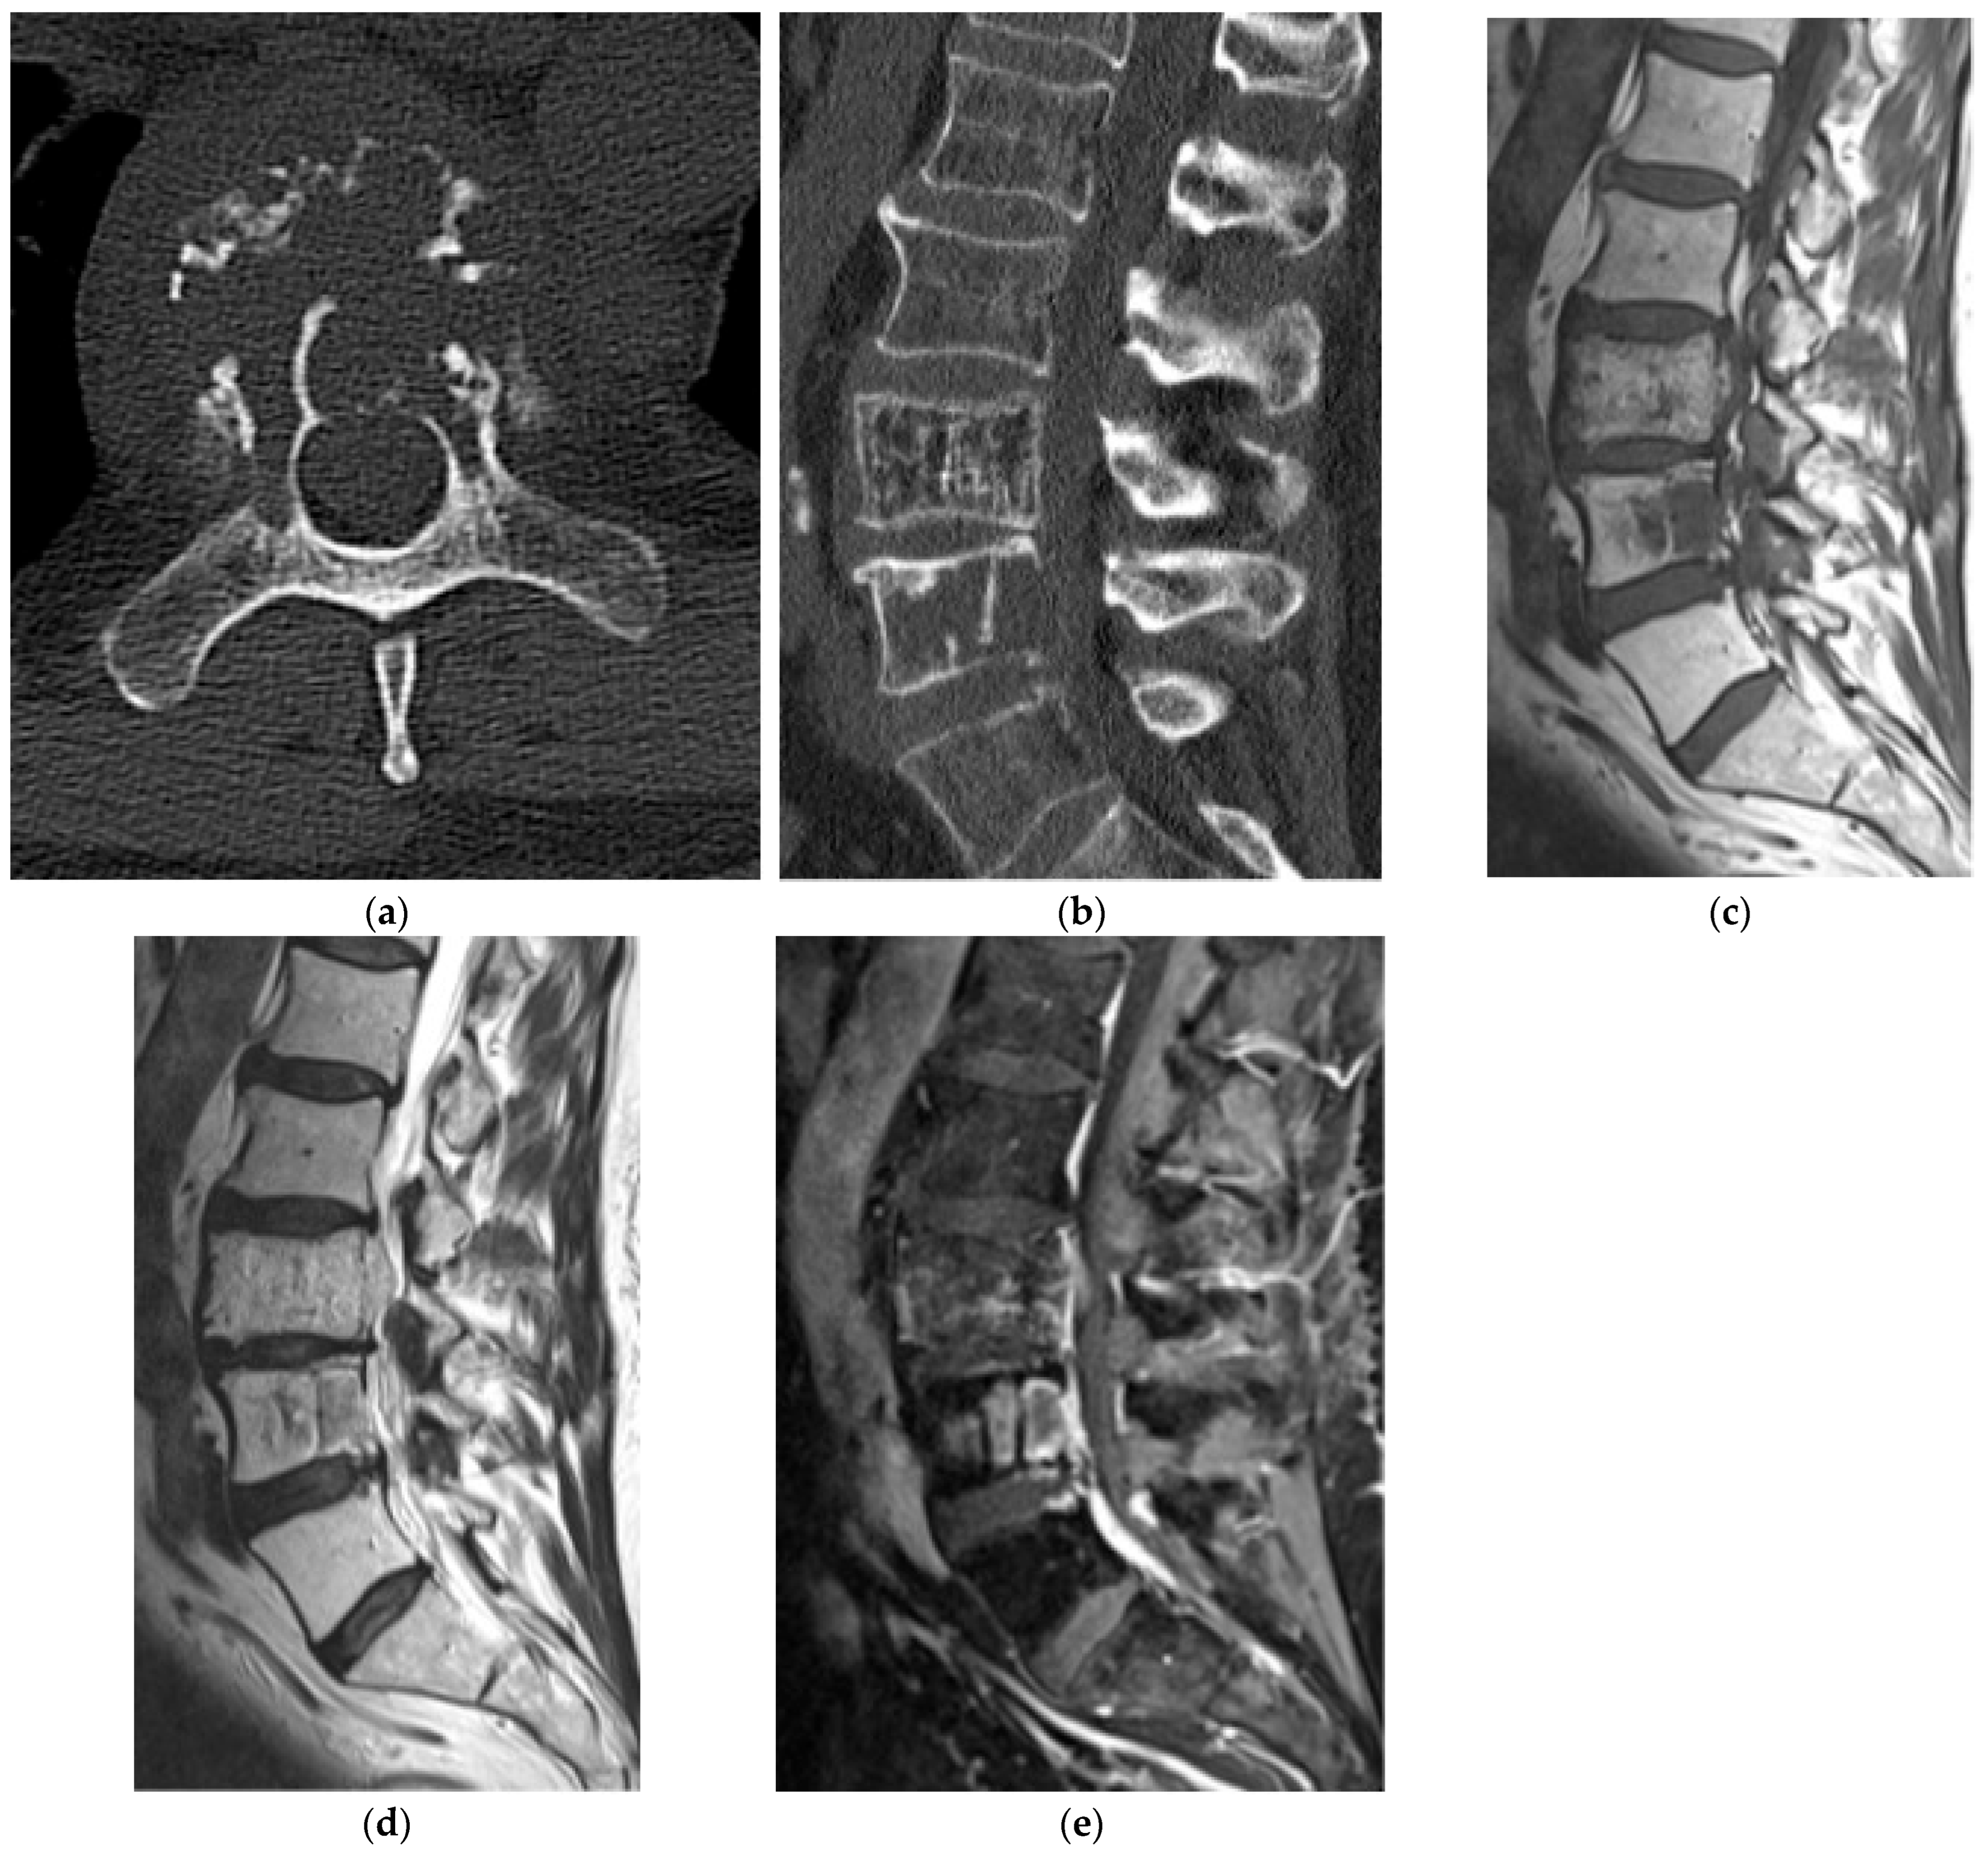

2.6. Fibro-Osseous

Fibrous Dysplasia

Paget’s Disease